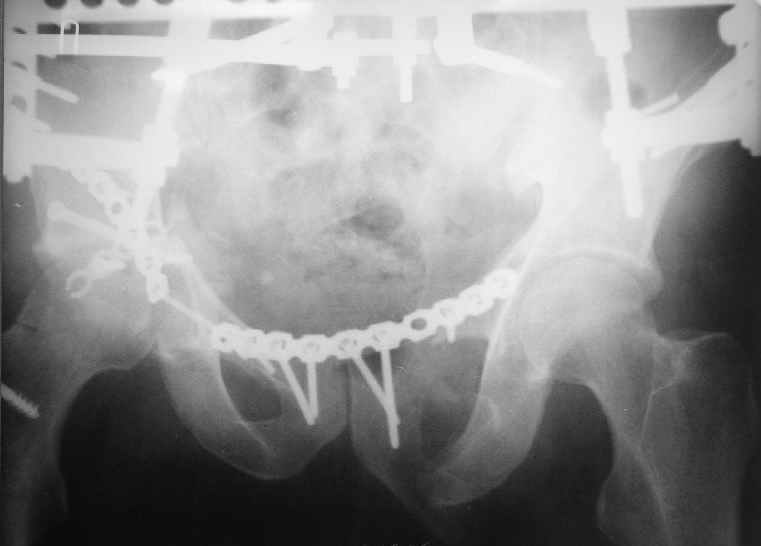

Уважаемый Антон, у Вашего больного имеется транстектальный поперечный перелом вертлужной впадины с переломом заднего края, перелом заднего типа, подвздошный вывих, возможна импрессия и повреждение нерва. Головка при этих повреждениях в нагружаемой части должна быть целой.

Доступ чрезвертельный, лучше Y образный, хотя при хорошем опыте можно и задне наружным (вертел придется отсекать).

Фиксация передней колонны трансфрактурным винтом, задней пластинами,мостовидной и упорной.

Разрыв лонного сочленения можно зафиксировать сразу после фиксации вертлуги из второго доступа.

Высылаю нечто подобное, аппарат пусть не смущает, просто больного оперировал через 2 месяца после травмы, а у него еще полный разрыв кп сочленения с контрлатеральной стороны.